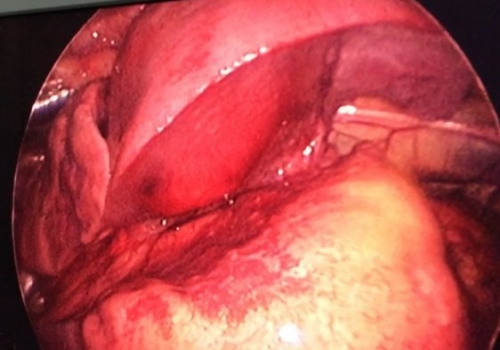

MediastinalTeratoma .Torokoskopik teratomanın eksiziyası

Daha bir çətin əməliyyat 8 yaşlı pasientdə döş boşluğunda törəmə- Ağciyərin orta payı üzərində böyük həcmli törəmə Teratoma. Torokoskopik törəmənin eksiziyası